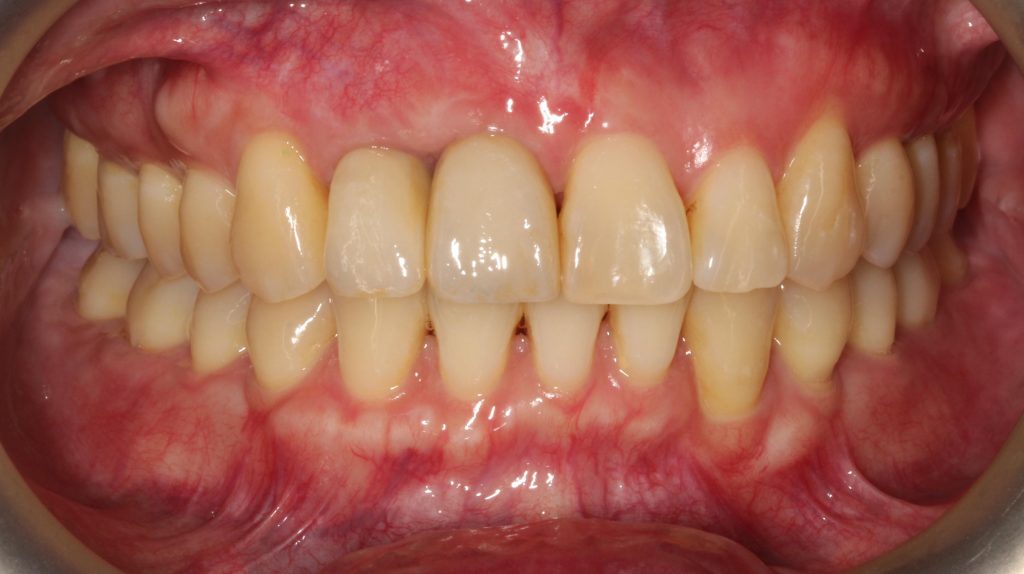

什麼是「牙冠增長術」,簡單說,即是修整牙齦和牙冠的比例,藉此來解決口腔內,每顆牙齒牙齦高低、位置落差所導致美觀上不協調的問題。